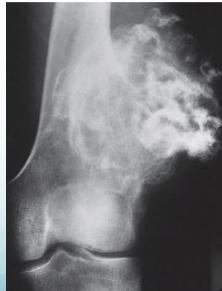

Osteoid Osteoma

- Small tumor (<1 cm)

- Young adults

- Pain, pain, pain:

- Typically relieved by Salicylates

- Sites: Femur, tibia, spine

- X-ray:

- Small radiolucent “nidus”

- Surrounded by sclerotic bone

- CT: Shows “nidus” better

- scan: hot

- Treatment: surgical excision, or thermal ablation

Source: Orthopedic Radiology. A Greenspan. Lippincott-Raven

Sources: Apley’s System of Orthop. And Fractures, http://openi.nlm.nih.gov/

Clinical Example

- 11 year old boy: Pain in left hip